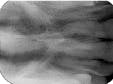

The bisecting-angle technique creates specific errors in vertical angulation, giving shortened images (see Radiograph 2 as an example of foreshortening) or lengthened images (see Radiograph 3 as an example of elongation). Substantially shortened images occur because there is too much vertical angulation. This causes distortion in the reproduction of the actual size of the tooth. The solution requires a decrease of the vertical angulation by at least 10 degrees.

Conversely, lengthened im-ages occur because there is not enough vertical angulation. Another reason is that the film is curved in the mouth. Increasing the vertical angulation by at least 10 degrees and repositioning the film to prevent bending will alleviate this distorted image.